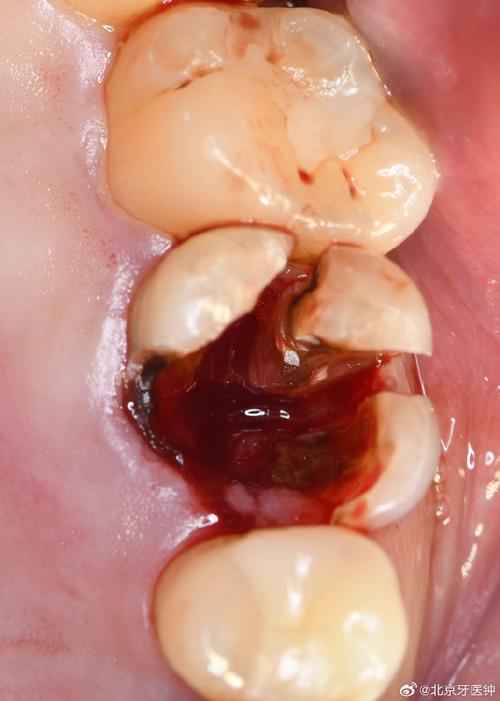

种牙植骨手术需在牙槽骨内制备种植窝、植入骨粉,这一过程可能损伤周围小血管,导致术后短期内少量渗血,属于正常现象,但若出血量较大或持续时间较长,可能与以下因素有关:

- 手术创伤:术中操作可能损伤牙龈黏膜、骨膜或小动脉,尤其骨粉植入后局部血供丰富,若缝合不严密或压迫不足,易引发出血。